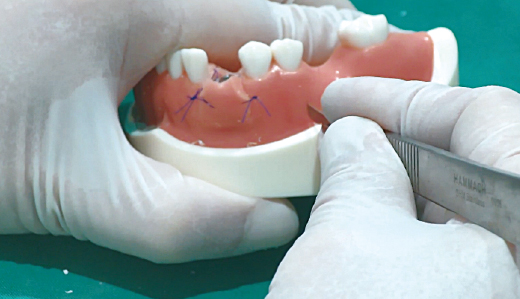

임플란트에 CowellBMP 코팅 시 : CowellBMP 용액을 원형 홈에 3~4방울 떨어트려서 임플란트에 코팅

1. Bone Carrier의 원형 홈에 먼저 rhBMP-2 용액을 주사

2. Hand-piece를 이용하여 원형 홈에 Fixture를 천천히 회전